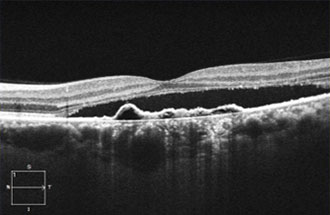

● 光干渉断層血管撮影機器(OCTA)

網膜疾患や緑内障の診断に用いられてきた光干渉断層計(OCT:optical coherence tomography)は、非侵襲的に網膜の断面を描出する機器でとして広く普及しています。当院では、8年前からOCTを導入し、網膜疾患と緑内障の診断と治療に活用してきました。

今回、新たにOCTに血管撮影の機能が付いた光干渉断層血管撮影機器(OCTA: OCT angiography、アンギオOCT)を導入いたしました。

これまで、網膜の血管を描出するには造影剤が必要でした。しかし、この最新の機器を用いることにより、網膜やその下にある脈絡膜血管を、造影剤を用いずに短時間で血管撮影できるようになりました。造影剤を用いた検査(蛍光眼底撮影)は、手間のかかる検査であるだけではなく、副作用のリスクもあるため、実施できない患者様もおられました。 OCTAは、これまでの造影剤を用いた検査の問題点を解決してくれる画期的な機器です。

OCTAを用いることで、これまでの網膜の断層撮影に加えて

① 加齢黄斑変性の脈絡膜新生血管の描出や治療効果の確認

パキコロイド新生血管症(PNV)に対するマイクロパルス閾値下レーザー治療を行い、網膜下液が吸収された症例。